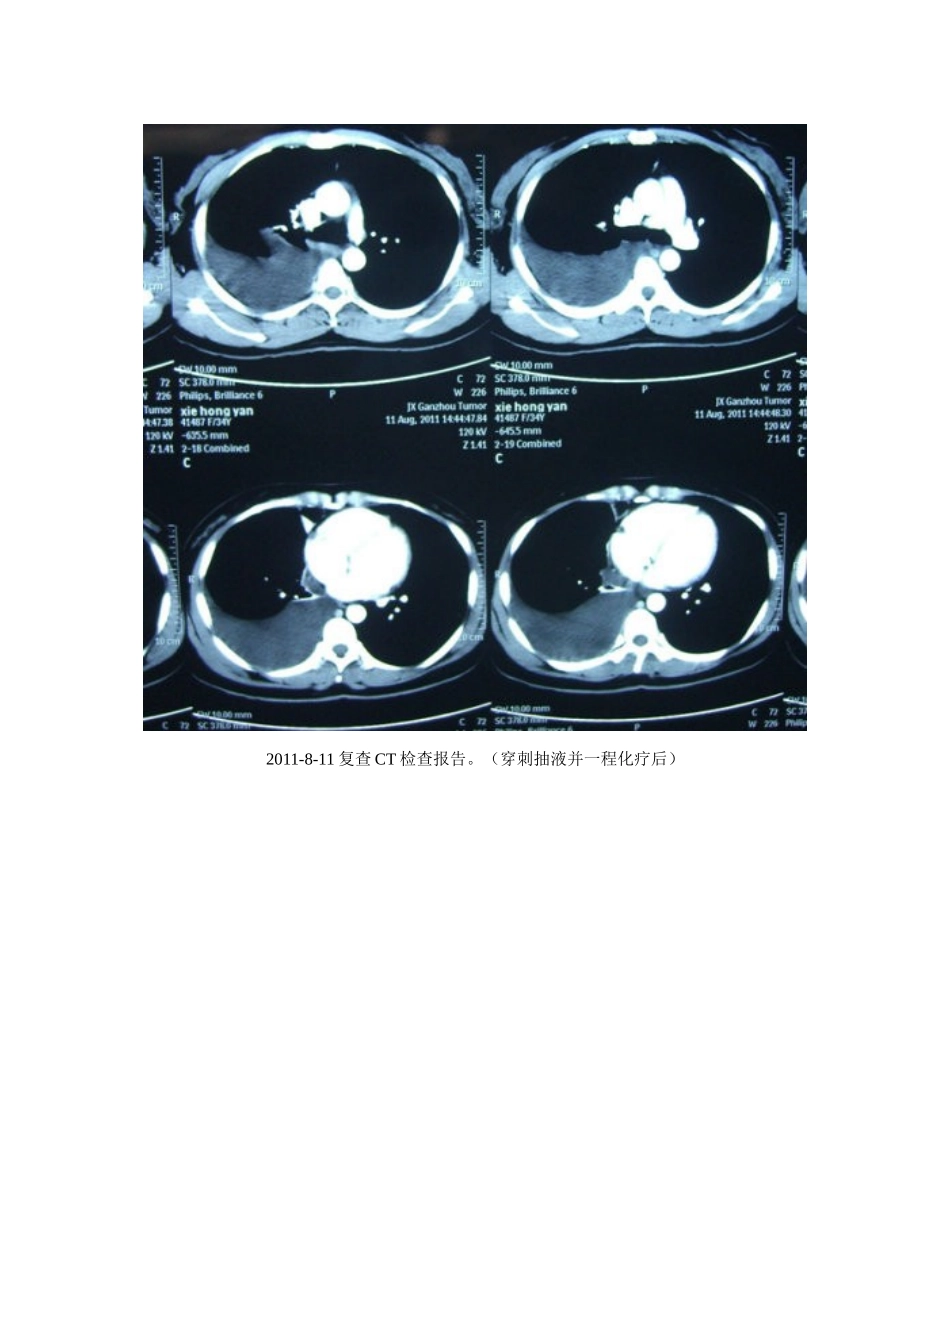

癌性胸腔积液----临床案例剖析----中华宋庆龄基金会特聘专家.。杨登平临床案例剖析1肺腺癌伴胸腔积液【病史摘要】:女性,34岁。患者于2011年7月份无明显诱因出现右侧胸痛,呈持续性痛,无发热盗汗及胸闷气紧,无头晕头疼,无恶心呕吐及其他不适。曾在当地医院治疗(具体治疗不详),症状无明显好转。于20011-7-9至2011-7-13在赣南医学院附属医院行胸部CT示右侧胸腔积液。胸水检查示:见腺癌细胞。于2011-7-15日转入赣州市三六二肿瘤医院行胸腔穿刺抽液及行一程化疗,化疗方案为:培美曲塞+顺铂;化疗过程顺利。于2011-8-11行第二程化疗,入院后完善相关检查,胸部CT示:右肺上叶见一不规则中度强化影,右侧胸腔大量积液,胃小弯淋巴结肿大;行胸腔穿刺抽液及对症支持治疗,予以吉西他滨+顺铂方案行二程化疗,患者除中度厌食及疲乏外,其他症状好转,于2011-8-25出院。出院二周余右胸又出现持续性疼痛并有牵扯感,到当地县医院胸腔X光扫示:右侧胸腔大量积液。遂放弃第三程化疗,于2011-9-28经人介绍到梅州天行健养生食疗中心进行食疗控制胸水和病情。患者疲乏、消瘦、厌食、咳嗽、脱发、右胸持续性疼痛并牵扯感明显。一:用加味开胃汤升提胃气,激活免疫。二:用牦牛蹄筋硬蛋白重建基质屏障(ECM,包围圈),修复侵袭破溃的胸膜。三:喝小米粥等粗粮,过午不食,保持气化和吸收。四:喝鲤鱼牛肉汤增强营养。五:喝鲜榨果汁。六:严格遵守饮食禁忌及养生之道等。20余天后出现饥饿感,症状好转。坚持3个月后于2011-11-28在梅州市人民医院行CT检查报告示:“右肺癌伴胸腔积液”治疗后复查,与2011-8-11日外院CT片对比,现片示:右肺上叶片影较前缩小、淡薄,纵膈窗大小约2.5*1.4cm,其周围支气管扩张,并见斑片状模糊影分布,病灶较前增多。:右肺上叶尖段纵膈旁可见一小结节,较前稍缩小。右肺中叶少许条索状影,边界清。双肺纹理粗乱,肺透亮度增高。双肺门未见增大。纵膈内未见肿大淋巴结。右胸积液已吸收,左侧胸腔未见积液。余大致同前。意见:1、“右肺癌伴右侧胸腔积液”治疗后复查,右肺上叶片块影及小结节较前有所缩小,右侧胸腔积液已吸收;2、考虑右肺上叶支气管扩张合并感染;3、慢性支气管炎、肺气肿征象,右肺中叶少许纤维灶。2011-8-11复查CT检查报告。(穿刺抽液并一程化疗后)2011-7-15胸部CT示:右肺上叶见一不规则中度强化结节影,右侧胸腔大量积液,胃小弯淋巴结肿大(穿刺抽液并胸水病理检查示:腺癌细胞)2011-11-28CT示右侧胸腔积液已吸收,左侧胸腔未见积液。2011-11-28胸部CT示“右肺癌伴右侧胸腔积液”治疗后复查,右肺上叶片块影及小结节较前有所缩小,右侧胸腔积液已吸收。【评述】:肺癌的细胞分为两大型:小细胞肺癌和非小细胞肺癌,非小细胞肺癌(NSCLC)又可以分为鳞癌、腺癌、大细胞等亚型。小细胞肺癌的特点是多见男性青少年,生长快,18天倍增一次,放化疗非常敏感,停药易复发,非常容易脑转移,化疗必须做到12次以上且愈后不佳。得了肺癌是不幸的,实话实说,得了肺腺癌是不幸中的不幸,肺腺癌的特点是多见女性和不抽烟的男性,小腺癌,大转移,转移早,复发快,脑转移,骨转移,非常容易出现胸水,放化疗不敏感,预后差,死亡率高。本案穿刺抽液病理诊断是肺腺癌,胸膜转移已有大量的癌性胸水。两次穿刺抽液并两次化疗,而反复大量胸水未能控制(化疗不敏感),并出现肺实质性损伤(慢性支气管炎、肺气肿征象,右肺中叶少许纤维灶等)副作用。本案例从2011-8-26日--2012-8-29日到本中心控制病变,CT提示现胸腔积液已完全吸收,病灶结节等缩小,说明癌性积液等病变已基本控制。临床表明养生食疗及牦牛蹄筋硬蛋白对恶性实体瘤控制病情是有益的、有效的。值得在原发肿瘤及控制肿瘤的复发和转移的基础研究与临床实践中作理性的尝试和探索。